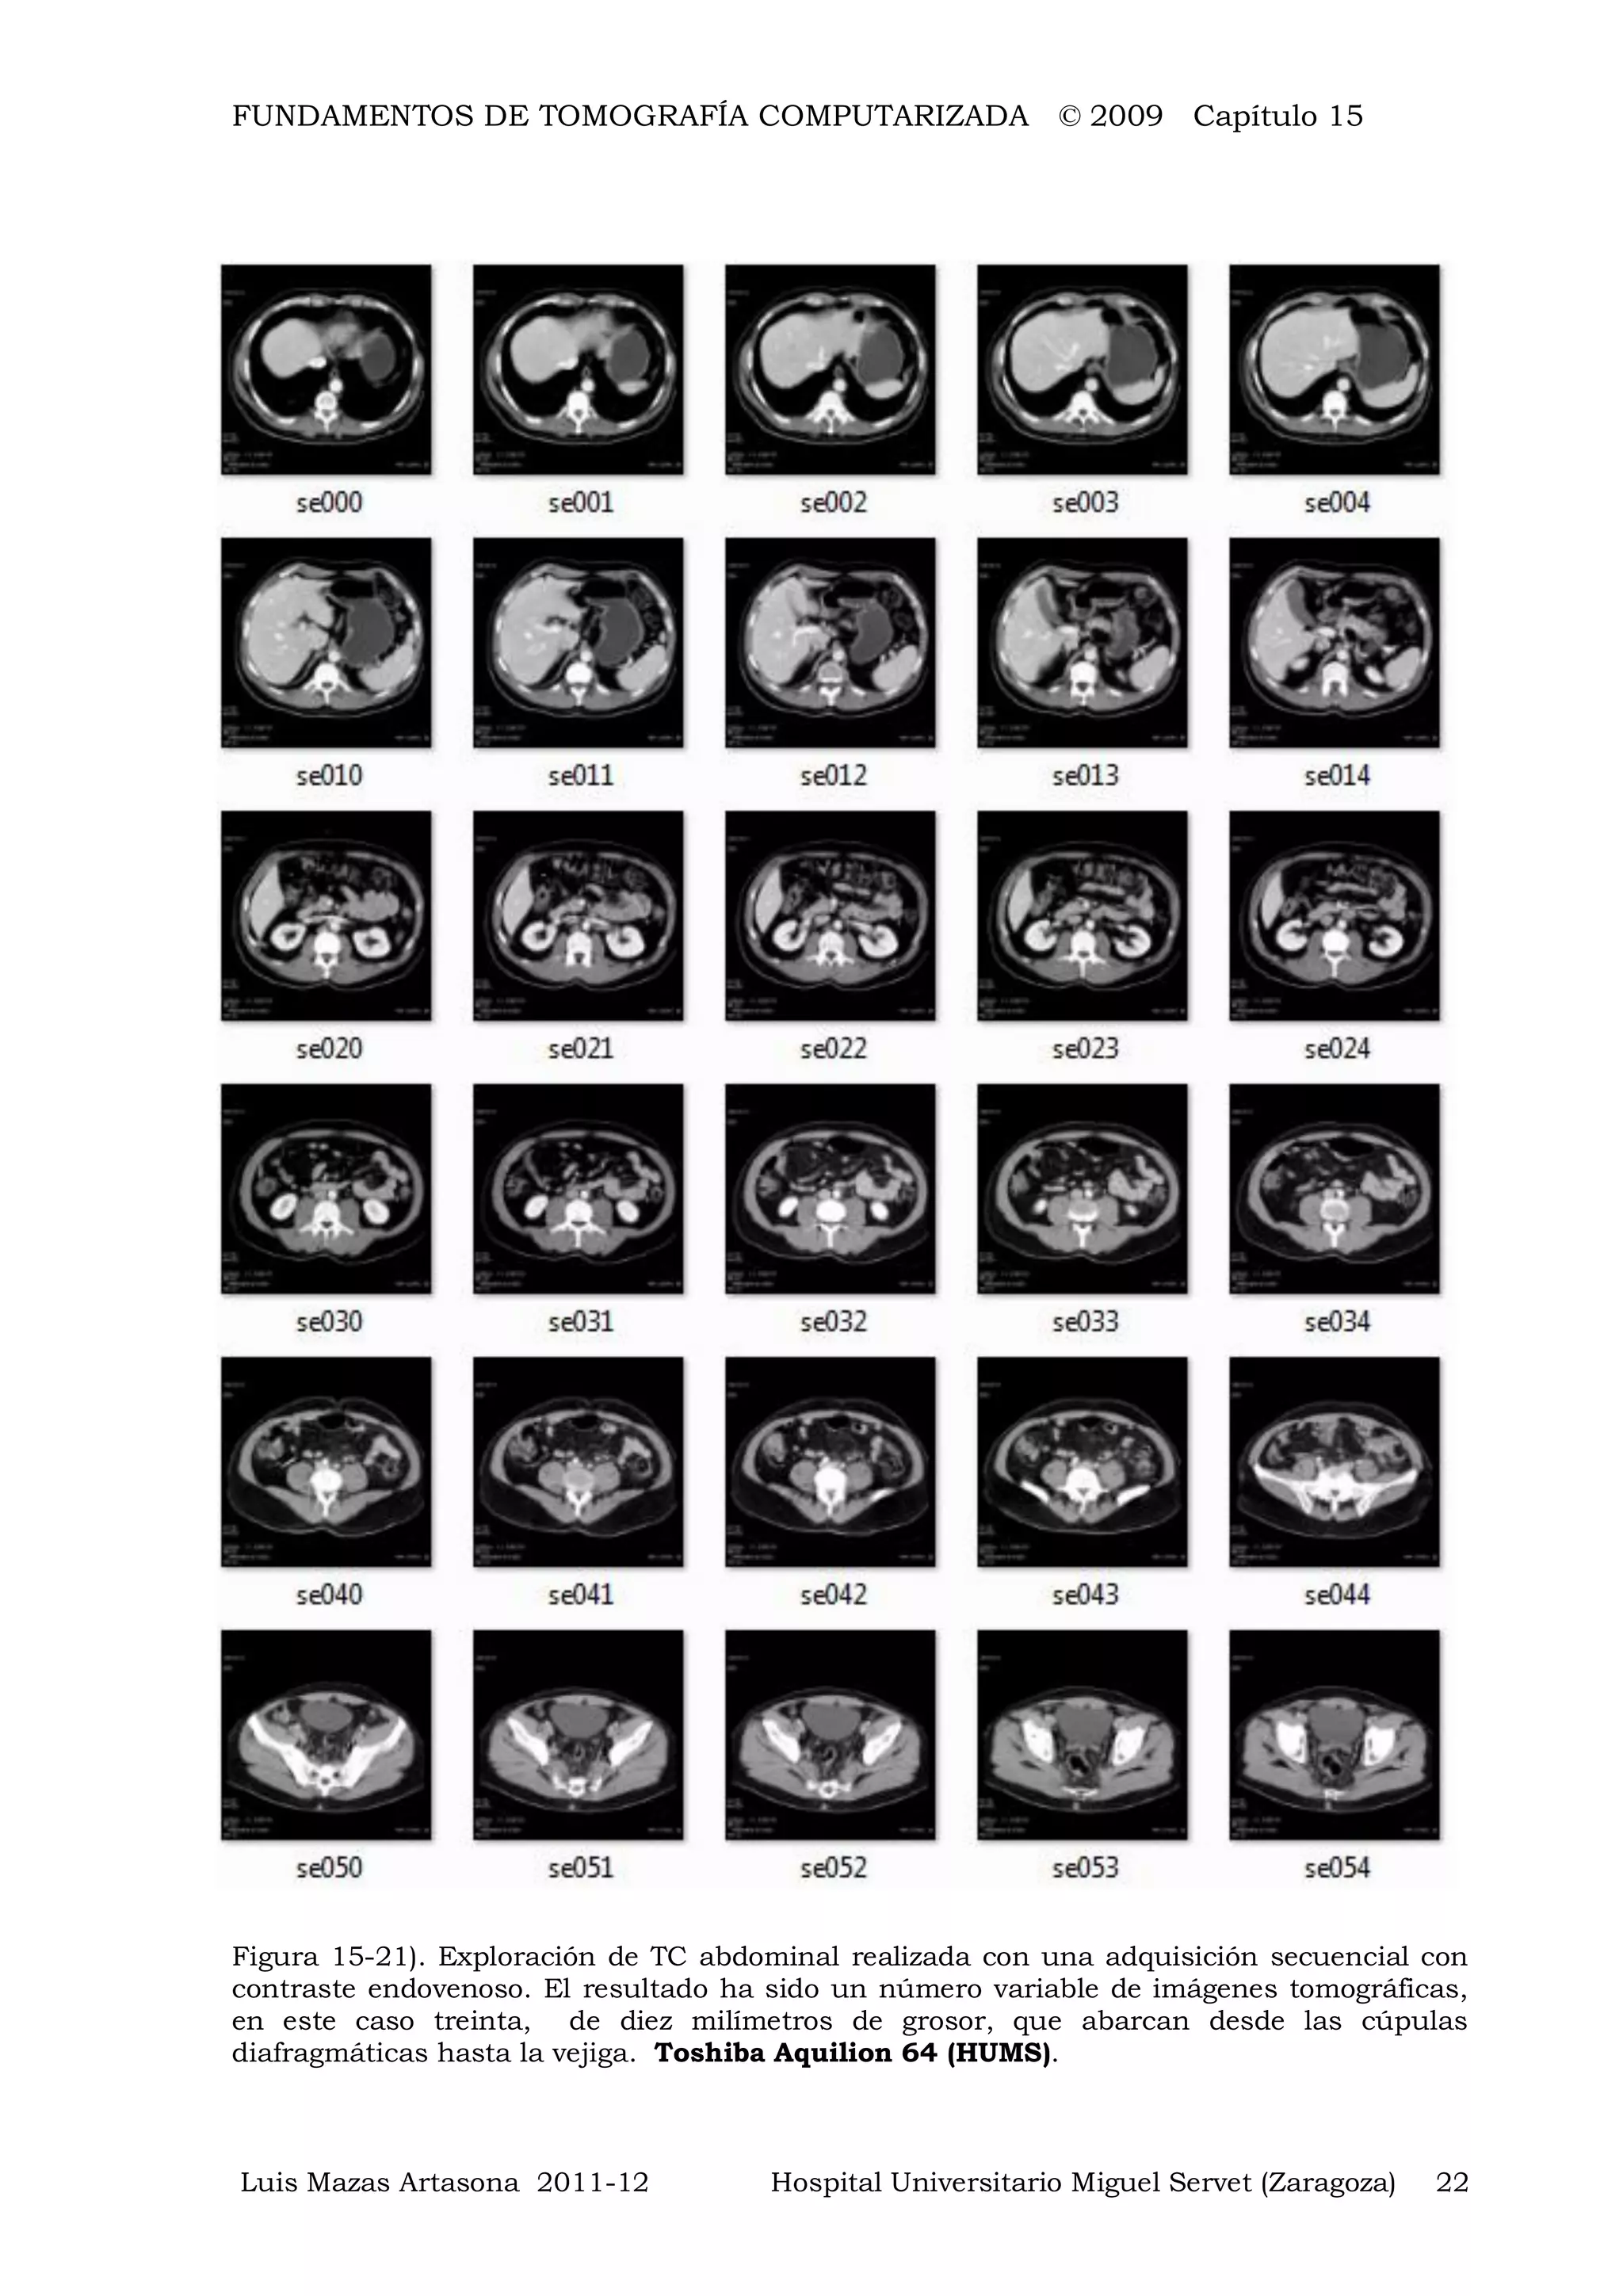

Figura 15-21). Exploración de TC abdominal realizada con una adquisición secuencial con

contraste endovenoso. El resultado ha sido un número variable de imágenes tomográficas,

en este caso treinta, de diez milímetros de grosor, que abarcan desde las cúpulas

diafragmáticas hasta la vejiga. Toshiba Aquilion 64 (HUMS).